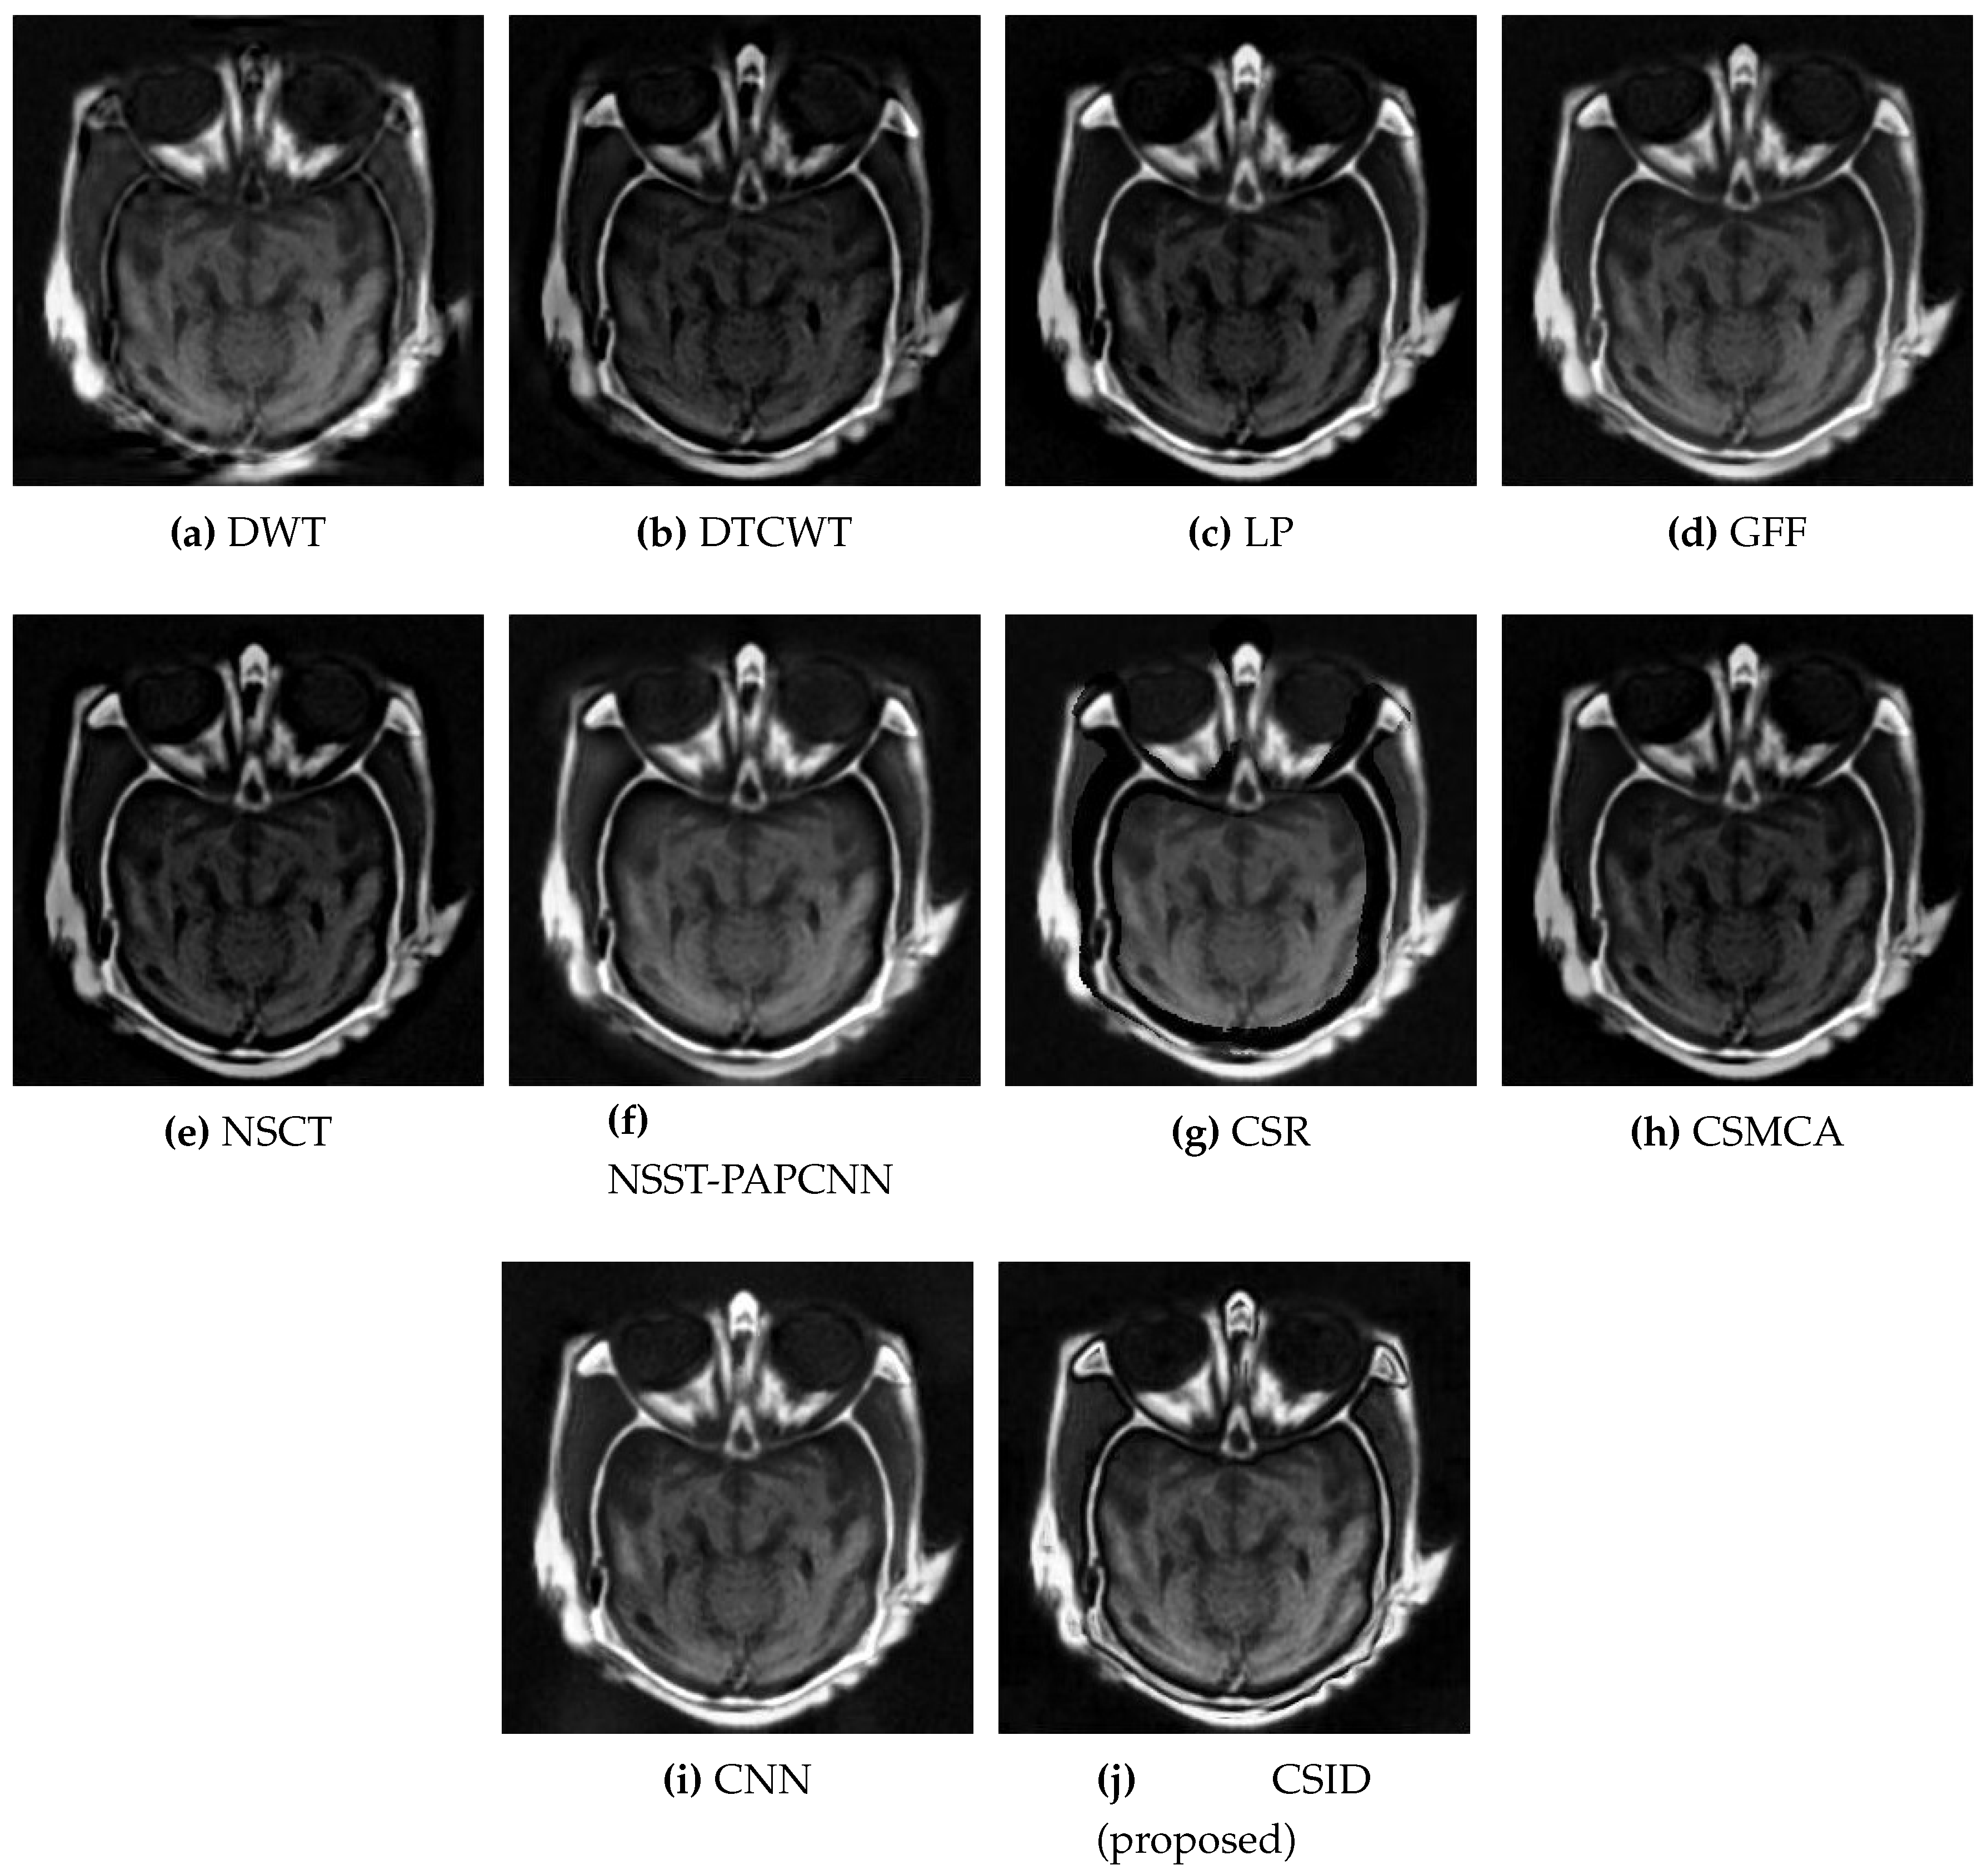

Finally, CSID and the aforementioned set of algorithms are evaluated using the Data-6 dataset, where Figure 10 demonstrates the corresponding qualitative results. All the algorithms, other than CSID, are unable of extracting detailed information that results in blurred fused images. To this end, our proposed CSID algorithm shows improved edge detection and provides enhanced contrast, in comparison with all the aforementioned algorithms that yield better visualization.

Figure 10. Comparative analysis, based upon visual observation, of the resultant fused images generated by the given set of algorithms using Data-6 dataset.